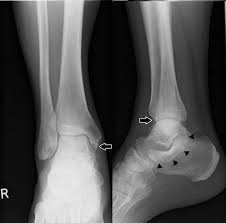

Stress fractures of the medial malleolus in the professional soccer player demonstrate excellent outcomes when treated with open reduction internal fixation and arthroscopic spur debridement anthony nguyenian beasleyjames calder knee surgery, sports traumatology, arthroscopy. Case contributed by dr henry knipe ◉ ◈. Medial malleolus and talus make up the medial side. The medial malleolus is the prominence on the inner side of the ankle, formed by the lower end of the tibia. What is the largest tendon of the calcaneus?

Traumatic dislocation of tibialis posterior presenting late as a bony spur. The relationship between spur formation, the medial tubercle of the calcaneus and intrinsic heel musculature results in a constant pulling effect on the plantar fascia resulting in an inflammatory. It may also involve injury to a ligament. What are treatment options for a bone spur? The medial malleolus is the largest of the three bone segments that form your ankle. Small well corticated bony fragments lies at the anterior aspect of the medial malleolus. The other two are the lateral and the posterior malleolus. The medial malleolus is the medial projection of bone from the distal tibia. Bone spurs are bony projections that develop along bone edges. The tibia (shin bone) is the medial bone of the leg and is larger than the fibula, with which it is paired (figure 3). The fibula is commonly shortened and externally rotated in a malunion, although only one of these may be present, determining the type of osteotomy and bone. Ankle joint dislocation is often associated with fracture of medial malleolus bone. Nkle sprain, medial malleolus, pseudoarthrosis radiographs of the medial malleolus showed jagged.